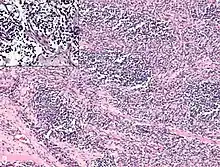

Rhabdomyosarcoma cells.

Rhabdomyosarcoma is often difficult to diagnose due to its similarities to other cancers and varying levels of differentiation. It is loosely classified as one of the small-blue-round-cell tumors due to its appearance on an H&E stain. Other cancers that share this classification include neuroblastoma, Ewing sarcoma, and lymphoma, and a diagnosis of RMS requires confident elimination of these morphologically similar diseases.[15] The defining diagnostic trait for RMS is confirmation of malignant skeletal muscle differentiation with myogenesis (presenting as a plump, pink cytoplasm) under light microscopy.[5] Cross striations may or may not be present. Accurate diagnosis is usually accomplished through immunohistochemical staining for muscle-specific proteins such as myogenin, muscle-specific actin, desmin, D-myosin, and myoD1.[26][35][36] Myogenin, in particular, has been shown to be highly specific to RMS,[37] although the diagnostic significance of each protein marker may vary depending on the type and location of the malignant cells. The alveolar type of RMS tends to have stronger muscle-specific protein staining. Electron microscopy may also aid in diagnosis, with the presence of actin and myosin or Z bands pointing to a positive diagnosis of RMS.[5][35] Classification into types and subtypes is accomplished through further analysis of cellular morphology (alveolar spacings, presence of cambium layer, aneuploidy, etc.) as well as genetic sequencing of tumor cells. Some genetic markers, such as the PAX3-FKHR fusion gene expression in alveolar RMS, can aid in diagnosis. Open biopsy is usually required to obtain sufficient tissue for accurate diagnosis. All findings must be considered in context, as no one trait is a definitive indicator for RMS.